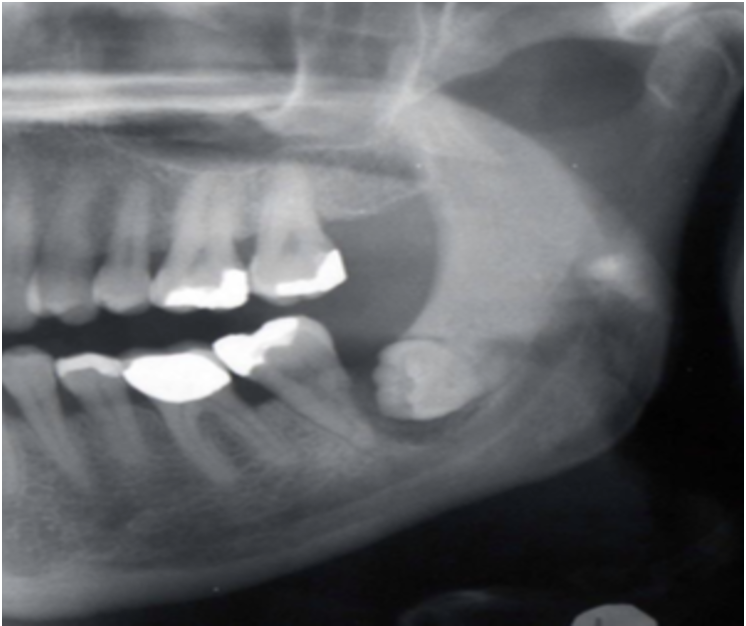

What can you observe in this radiograph?

What condition does this show?

Enlargement of pericoronal space

Chronic Pericoronitis